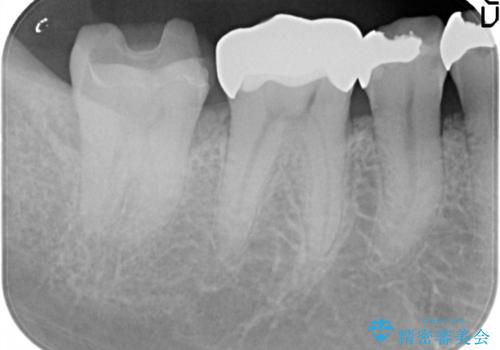

セラミッククラウンによるむし歯治療

- 他院で入れたセラミックインレーがかけたことを主訴に来院されました。

他の部位にもむし歯を認めたため、優先度の高い歯から治療を行っております。

咬合力が強くかかる部分には欠けるリスクのほとんどない金属を用いることが最良ですが審美性に劣ります。

今回は白い材料での修復を希望されたため、欠けるリスクが高いセラミックインレーは避け、セラミッククラウンにて治療を行いました。